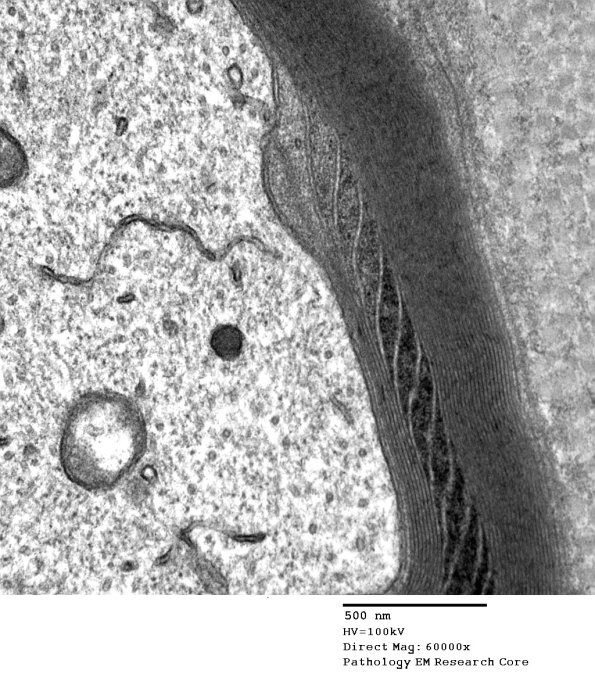

7A3,4 Notice in this case that the SLC ends at the adaxonal space adjacent to the axon. (Electron micrograph)